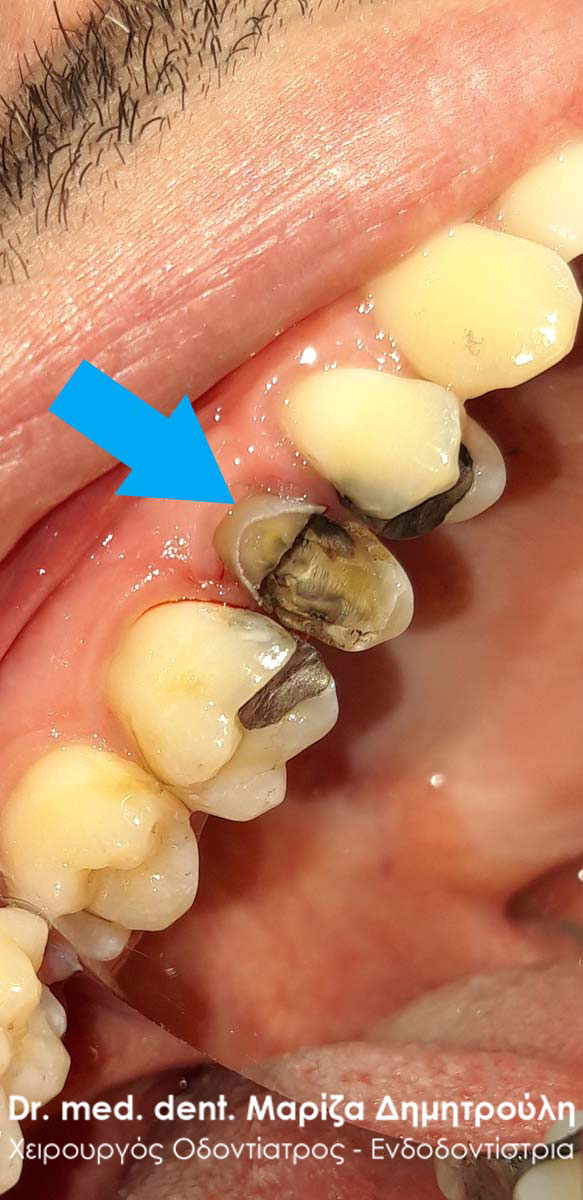

Ο πρώτος γόμφιος στην αριστερή πλευρά της κάτω γνάθου είχε απονευρωθεί στο παρελθόν. Ο ασθενής δεν θέλησε να καλύψει το δόντι με θήκη, ώστε να είναι πλήρως προστατευμένο με αποτέλεσμα το δόντι να σπάσει (όπως φαίνεται στην αρχική εικόνα). Η λύση θεραπείας ήταν η κατασκευή στεφάνης δοντιού, αφού προηγουμένως το δόντι τροχίστηκε καταλλήλως και ο οδοντοτεχνίτης κατασκεύασε την ολοκεραμική θήκη ζιρκονίου.

Το δόντι είναι πλέον πλήρως προστατευμένο και μπορεί να αντέξει στο πέρασμα των χρόνων.

ΠΡΙΝ